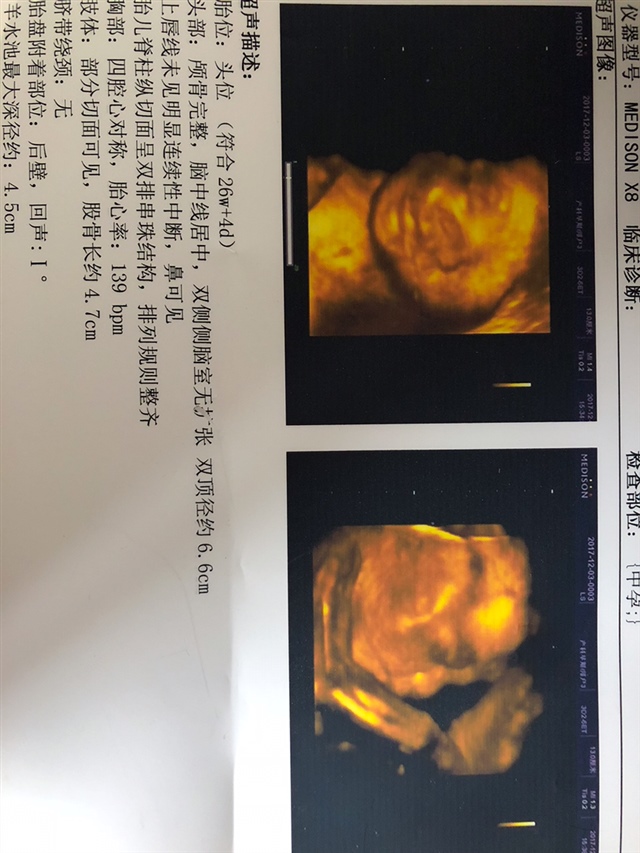

孕24周+4天